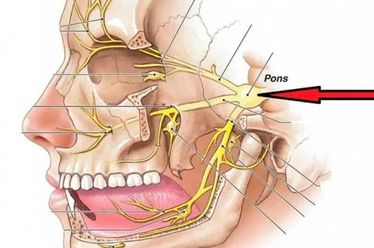

Os sintomas de um meningioma variam muito dependendo de sua localização e tamanho, mas alguns sinais gerais merecem atenção. Dores de cabeça que mudam de padrão ou frequência, convulsões em pessoas que nunca tiveram crises antes, alterações de personalidade, perda de equilíbrio, dificuldades na fala ou na visão são indicativos importantes. A pressão intracraniana elevada também pode causar náuseas e vômitos, especialmente pela manhã.

O tratamento cirúrgico é a principal abordagem para a maioria dos tumores acessíveis. O objetivo é remover a maior quantidade possível do tumor com segurança, preservando as funções neurológicas vitais. Hoje, utilizamos tecnologias como a neuronaqueção e o monitoramento eletrofisiológico intraoperatório, que funcionam como um “GPS” para o cirurgião, aumentando a precisão e a segurança do procedimento.